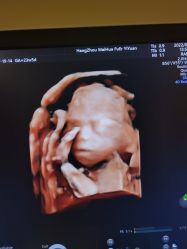

• 杭州贝瑞斯美华妇儿医院·早孕·产检·儿科

肚里圆圆 上传于 22-07-20 | 报错